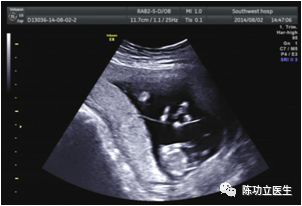

超声表现:双胎峰。超声医生如果在报告中如果能附上绒毛膜性的图,不胜感激哟。

T征:(单绒双羊)